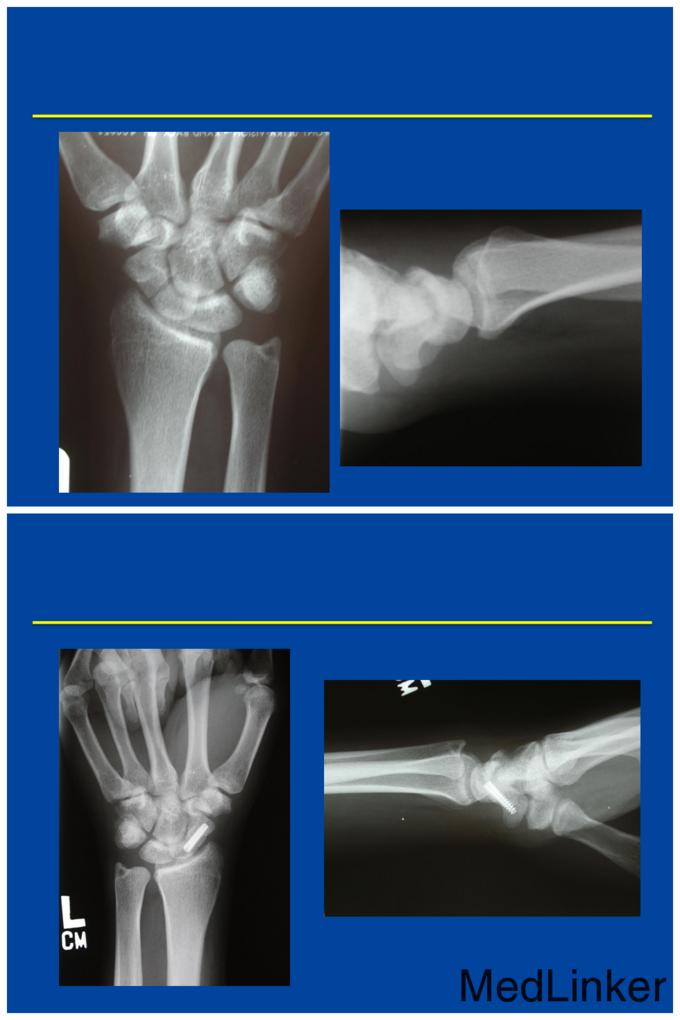

本篇学习目的是: 1 回顾腕舟骨骨折的基本诊断 2 探讨腕舟骨影像检查的几种方法 3 非手术与手术治疗的选择 4 腕舟骨骨不连的处理 Dawn M. LaPorte, MD Oorthopadic Surgery, Johns Hopkins 拉波特教授于麻省理工学院本科毕业后就读于约翰霍普金斯大学医学院。曾分别于翰霍普金斯大学医学院和柯蒂斯中心国家手与上肢外科完成住院医师培训。临床上致力于手和上肢外科。自2001年起已担任过8年的约翰霍普金斯大学住院医师培训项目负责人。现任约翰霍普金斯大学医学院骨外科教育副主席,美国手外科协会住院医师培训委员会主席(ASSH),骨科住院医师管理委员会和骨科科住院医师审查委员会委员。